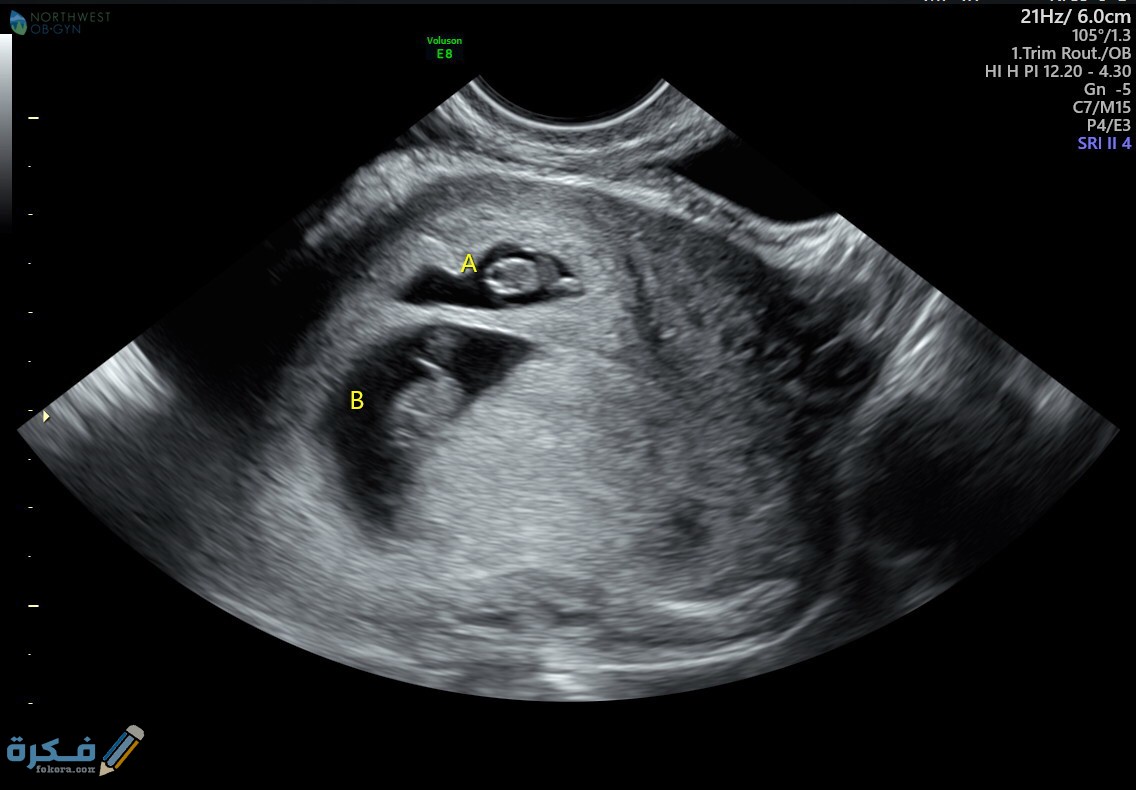

أكمل القراءة »اسباب متلازمة التوأم المتلاشي او الخفي من خلال موقع فكرة Fekera.com ، تعاني العديد من النساء حول العالم بظاهرة ما…